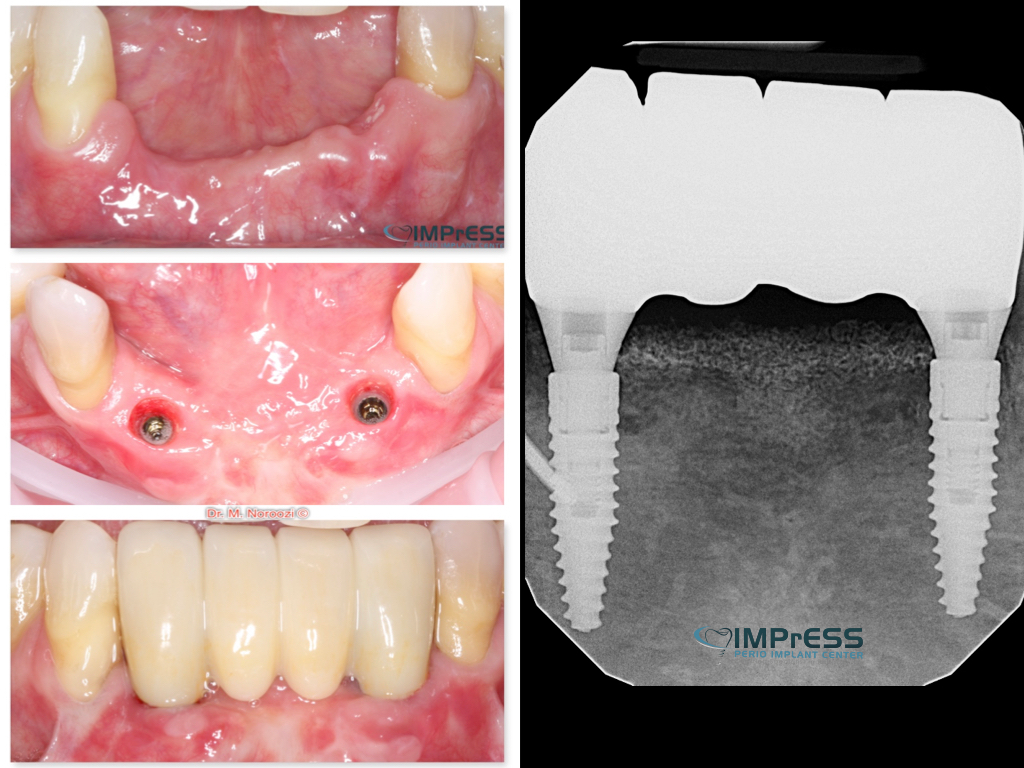

Full Mouth Reconstruction with Fixed Implant Bridge – All on X